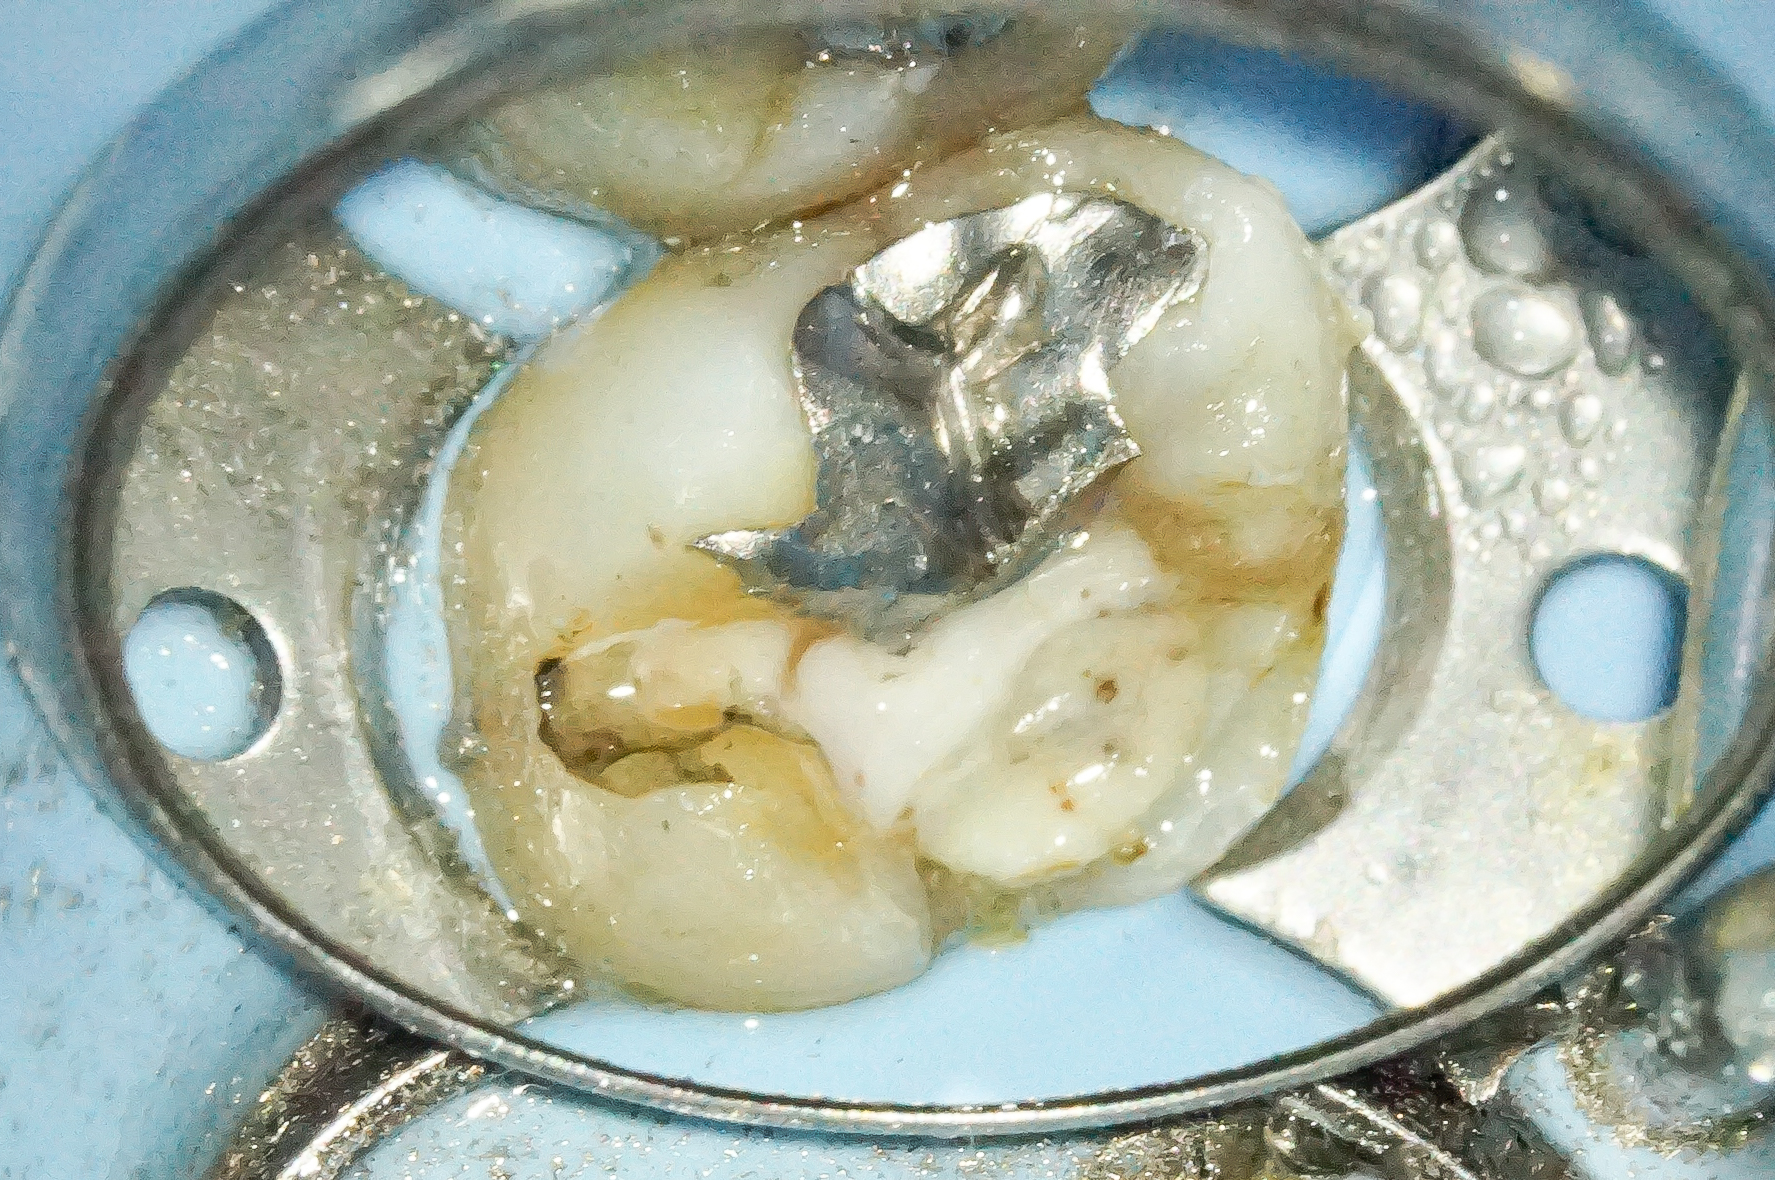

熱が発生しにくい切削バーを使ってメタルインレーを除去します。

この際、削る必要のない天然歯の部分を傷つけないように細心の注意を払います。

メタルインレーを完全に除去したところです。

一見大きな問題があるようには見えませんが…